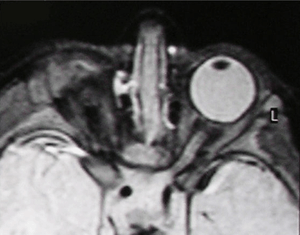

Right-sided anophthalmia (MR image)

MRI/CT

MRIs and CTs can be used to scan the brain and orbits. Radiologists use this to assess the internal structures of the globe, the optic nerve and extraocular muscles, and brain anatomy.